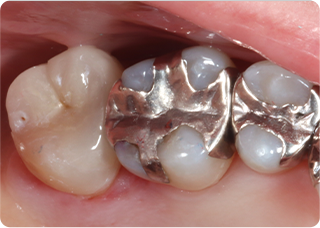

メタルフリー治療

セラミッククラウン症例①

術前

仮歯

技工物

術後

| 主訴 | 見た目を綺麗にしてほしい |

| 治療期間/回数 | 3ヵ月、5回 |

| 価格(税込) | 363,000円(税込) |

| リスク・副作用 | セラミック破損の可能性 |

| ポイント | 自然な色、形となるようにオーダーメイドでセラミックを盛ってクラウンを作製した。 |